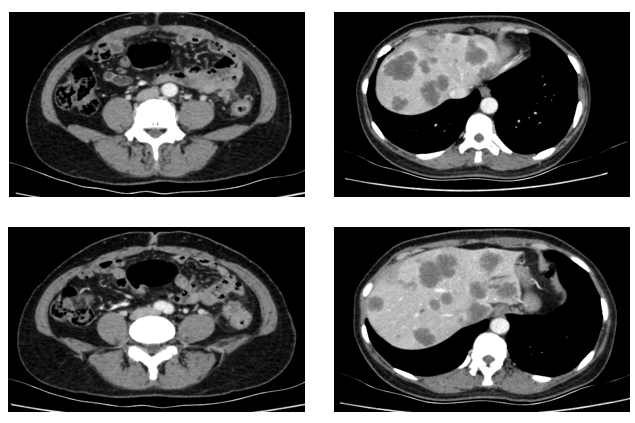

于2021-12-03、2021-12-27给予伊尼妥单抗+吡咯替尼方案治疗2周期。2022.1.19始给予患者伊尼妥单抗+吡咯替尼+替雷利珠单抗治疗,两周期,四周期时的疗效评估可以看到,肺上病灶明显缩小,甚至有的病灶消失,肿瘤标志物也在持续下降。

肿瘤第二次进展(2022-8-3):在二线治疗7月余后,肿瘤标志物升高,CT也显示,肺上的病灶增大,患者双靶向+免疫治疗进展。